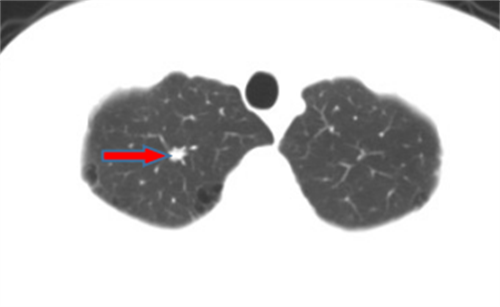

李先生,45岁,发现右上肺结节2年,近期长大,术后病理诊断肺结节为炎性假瘤。